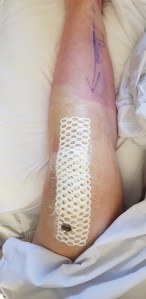

When I had the left ankle done in 2023, by the time I was in a moonboot and on crutches I could drive to the gym and do the weighted back exercises I needed to do to maintain my posterior chain strength. With the right ankle, obviously I couldn’t drive for an additional month. Then, two weeks after I could drive, I was back in hospital for a nasal/sinus infection. Essentially immobile again.

Once that was out of the way and I was back on my feet, I realised as I was walking that my posture was a disaster. I tried to stand up straight. Bottom line, I couldn’t. It wasn’t painful, I just could not straighten my back. I was horrified, as I knew this would not end well unless I did something about it.

Yes, I consulted my Exercise Physiologist and he gave me some specific rehab exercises to help. I increased (very carefully) my weight bearing posterior chain exercises. Now, almost a month after I detected the problem, I am almost back to where I was when I went in for surgery on December 2, 2025. I had not expected the de-conditioning to occur in that timeframe, although with hindsight, I should have.

Getting the situation corrected has not been painless. Mostly at the end of the day my lower back has expressed its discontent. There have been heat packs, Voltaren Gel, Panadol Osteo and a couple of days over that four weeks I have resorted to “the big guns”. However, I’ve reconditioned my back! Yay!